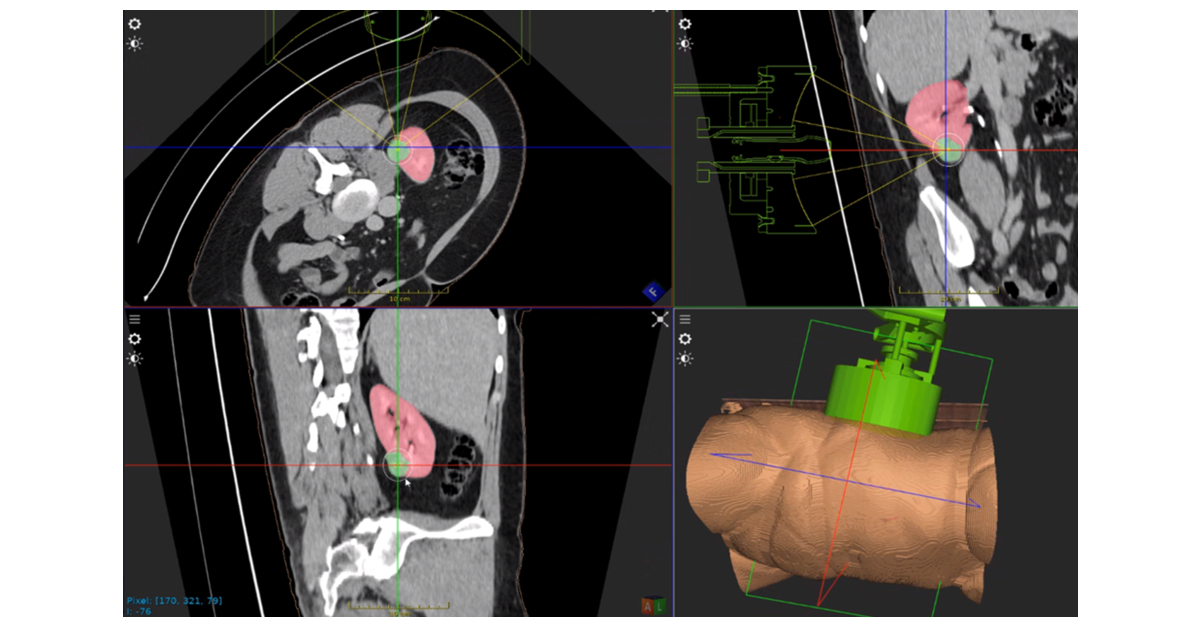

科大發現東亞人群阿茲海默症保護性遺傳因素揭示疾病機制】 在有關阿茲海默症領域中,SORL1基因(分揀蛋白相關受體L1基因)的研究備受關注,因某些SORL1基因變異對阿茲海默症有保護作用,使其成為疾病干預的潛在靶點,然而大多數相關研究只集中於歐洲人群。香港科技大學 , HistoSonics 在全球首开先河,运用Edison®组织摧毁术系统治疗肾肿瘤| Business Wire,

HistoSonics 在全球首开先河,运用Edison®组织摧毁术系统治疗肾肿瘤| Business Wire, 口服SERD类药物在激素受体阳性乳腺癌中的应用新进展| 辉瑞医学信息网站